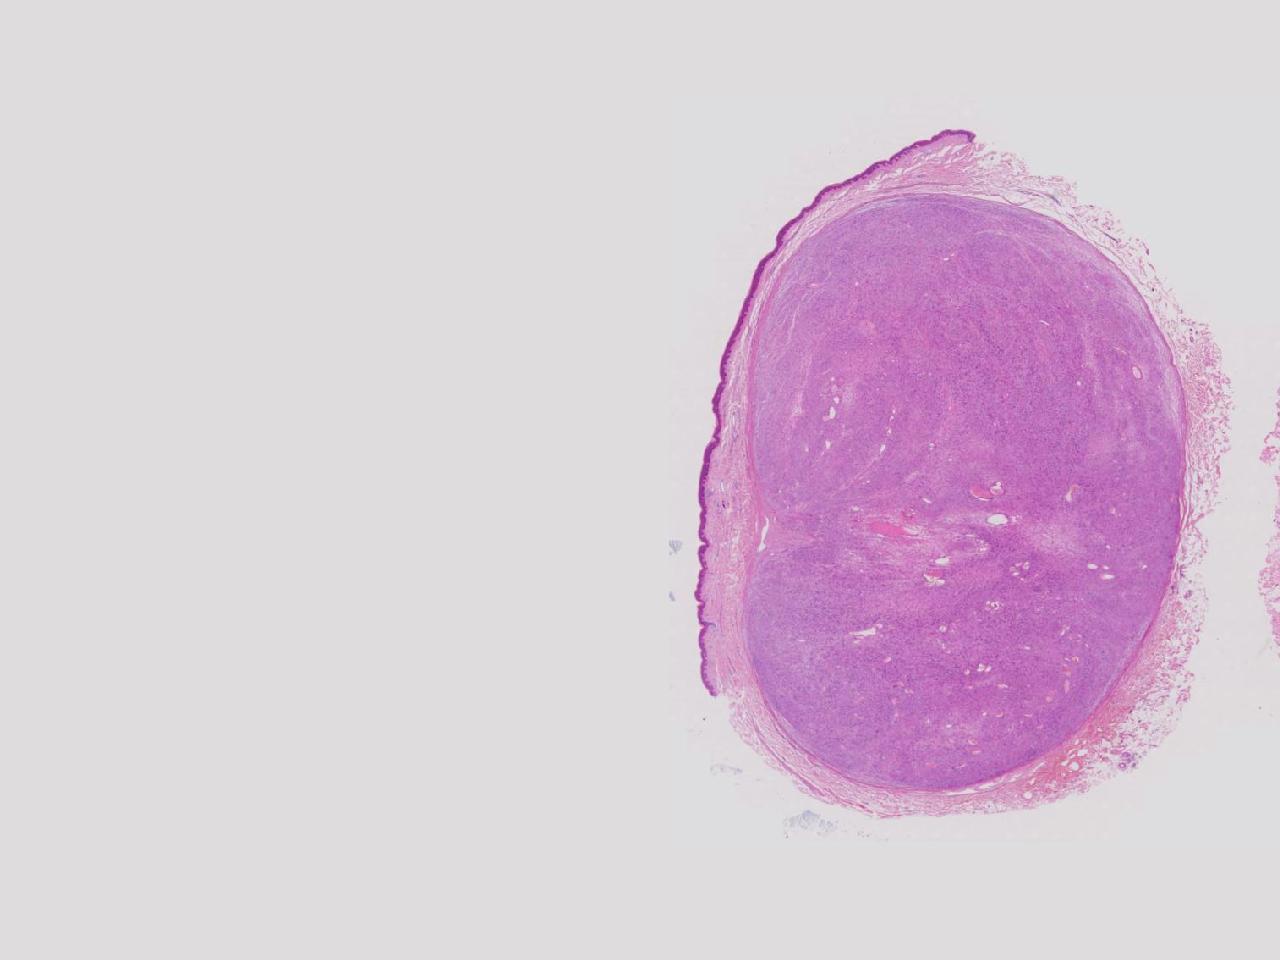

血管平滑肌瘤? 其他?

大体所见

卵圆形肿物一个,直径1.6厘米,上附皮肤。肿物切面灰黄实性,质中等。

考虑:结节性筋膜炎

完整的包膜。 首先还是考虑神经鞘。

神经鞘瘤。

建议除外平滑肌瘤,做IHC是更好的鉴别方式